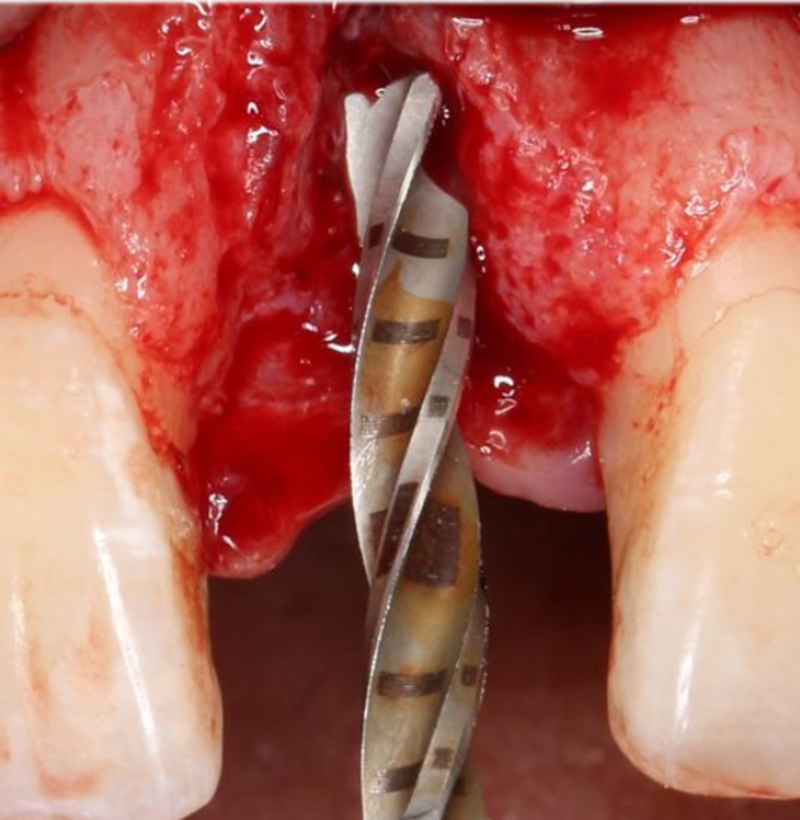

2.8mm 擴孔鉆按種植體軸向擴大窩洞△

在實時導(dǎo)航系統(tǒng)中,實時引導(dǎo)擴孔鉆按照術(shù)前設(shè)計種植體軸向及深度進行擴孔△